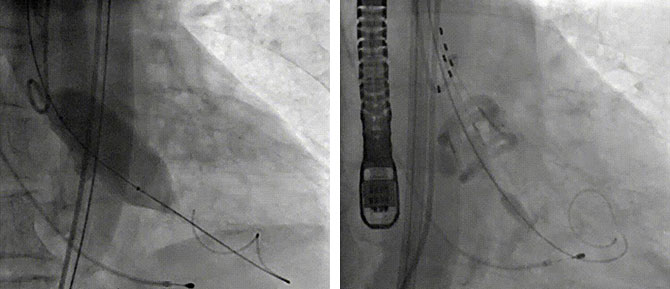

球囊扩张狭窄的瓣膜(左图),Silara 主动脉瓣膜提拉至瓣环水平,精准定位瓣膜,造影剂显示瓣膜功能良好,完成固化(右图)